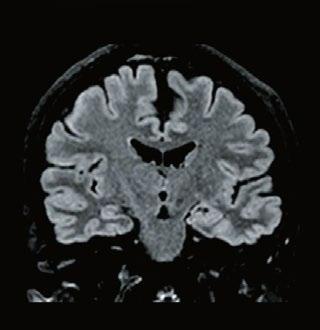

Fig 1: Next generation MRI is being used to gather data on brain tissue volumes Dr. Steve McNally

From this season at Manchester United Football Club, we have started to gather data by using MRI (see fig 1) to measure volumes of brain tissue in specific areas, to monitor for a decrease in volumes over time. If the volumes become unusual or deviate from the norms that we would expect, it may help us identify early changes of CTE that need closer monitoring. This is a new, long-term data gathering study in our cohort of players that has been facilitated with the new next generation MRI3 now in place at our medical centre.

MRI is also an excellent choice of tool for the diagnosing and monitoring of Chronic Traumatic Encephalopathy (CTE), the result of repetitive brain trauma from blows to the head and repeated episodes of concussion, which in football may have come from player contact or heading the ball. It is a hot topic in all contact sports such as boxing, rugby and martial arts and follows research at the University of California, Los Angeles (UCLA) using MRI as the option to explore CTE without any dose implications to patients2

32 // VISIONS SPECIAL